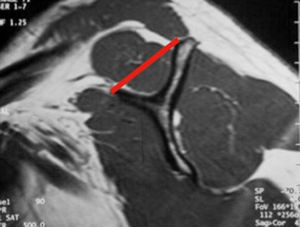

Clasificación de acuerdo con la calidad del tendónLa calidad del tendón se puede evaluar por TC o RM y su función principal es determinar si el tendón, por su calidad, es reparable. La clasificación más usada es la clasificación de Goutallier (tabla 5), basada en la existencia de infiltración grasa en imágenes de TC. Fuchs ha publicado también una clasificación similar con el uso de RM (figs. 3–6).